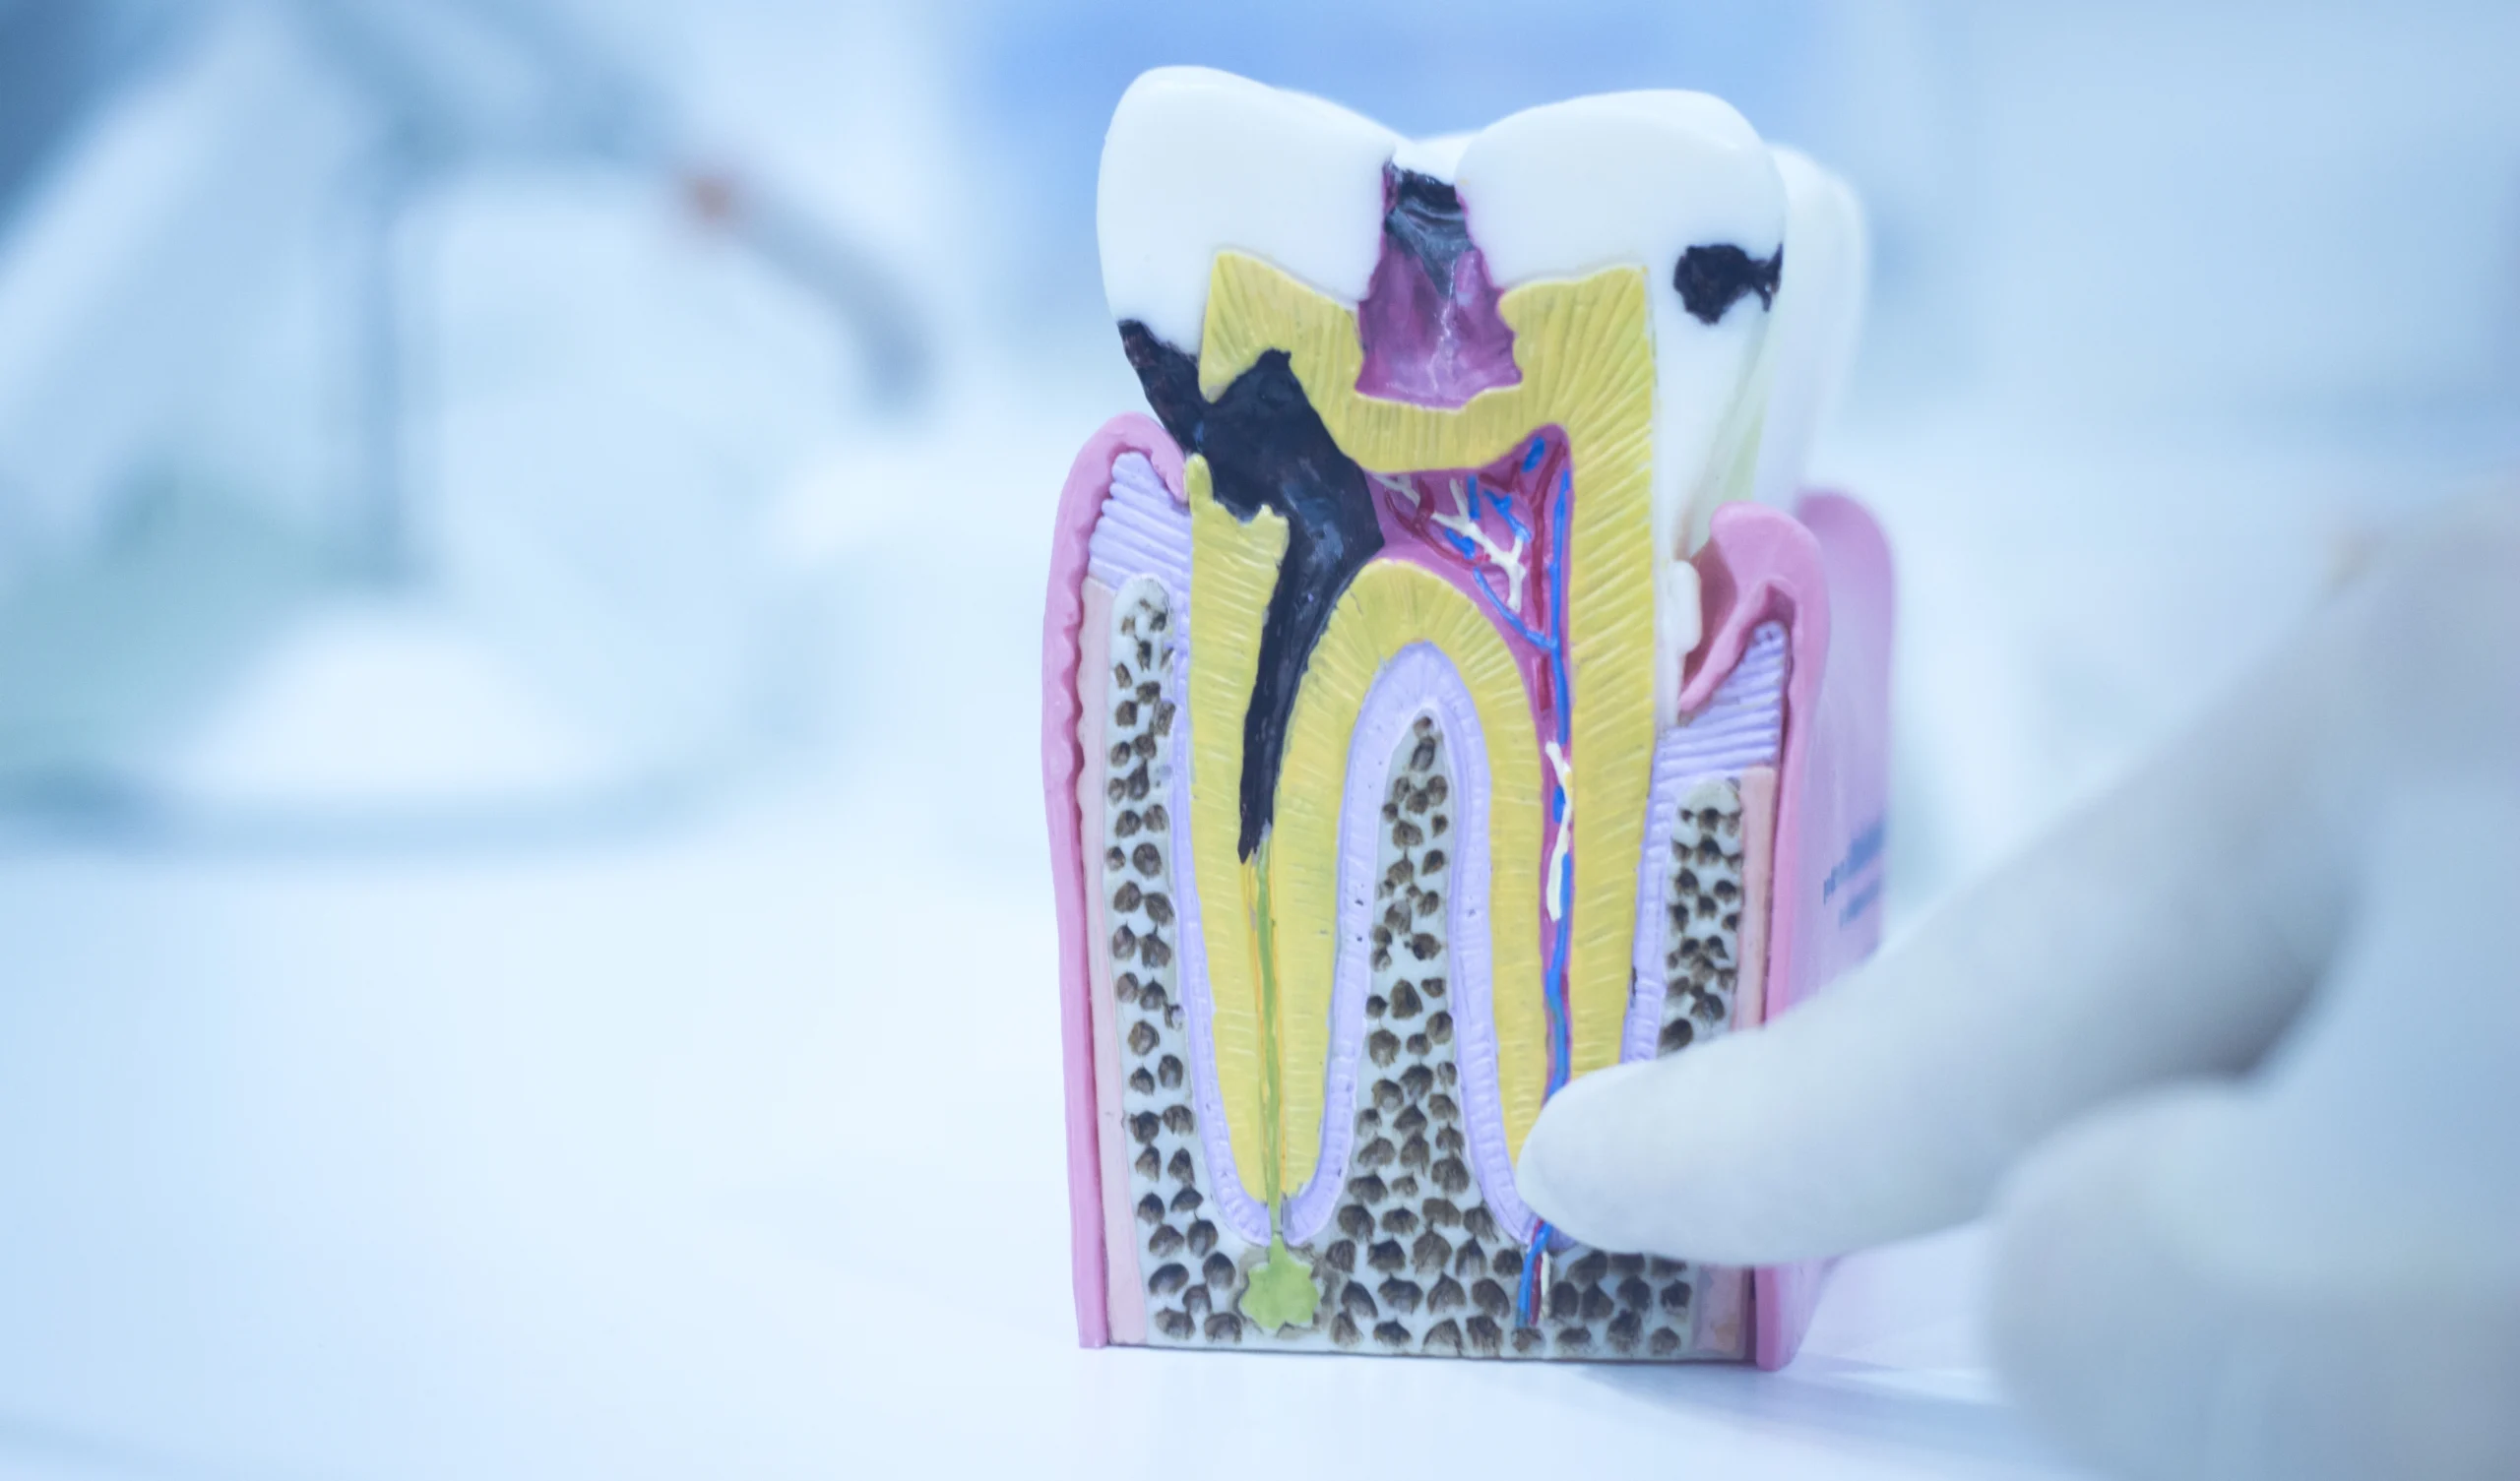

عصبکشی یکی از درمانهای رایج دندان پزشکی است که برای نجات دندان از کشیده شدن انجام میشود. در این روش، عصب و پالپ آسیبدیده از داخل دندان خارج و فضای خالی با مواد مخصوص پر میشود. بسیاری از بیماران تصور میکنند بعد از عصبکشی، دندان کاملاً بیدرد خواهد شد؛ اما گاهی اوقات درد دندان بعد از عصبکشی ادامه دارد یا حتی پس از مدتی بازمیگردد. در این مقاله به بررسی علتهای احتمالی درد دندان عصبکشی شده میپردازیم. اگر قصد عصب کشی دندان در رشت را دارید، تا انتهای مقاله با ما همراه باشید.

3. پر شدن ناقص یا بیش از حد کانالها

در عصبکشی، کانالهای ریشه باید تا حد مشخصی تمیز و با مواد پرکننده پر شوند. اگر کانالها بهصورت ناقص تمیز یا پر شوند، یا برعکس مواد پرکننده از انتهای ریشه خارج شود، میتواند باعث تحریک بافتهای اطراف و درد شود.

4. ترک یا شکستگی ریشه دندان

گاهی حتی بعد از عصبکشی موفق، وجود ترکهای ریز در ریشه میتواند منجر به نفوذ باکتریها و بروز درد مزمن شود. این ترکها در عکسهای معمولی همیشه قابل مشاهده نیستند، ولی درد مبهم یا تیرکشندهای ایجاد میکنند که به مرور زمان تشدید میشود. در چنین شرایطی، دندانپزشک ممکن است پیشنهاد روکشگذاری یا در صورت غیرقابل ترمیم بودن، کشیدن دندان را مطرح کند.